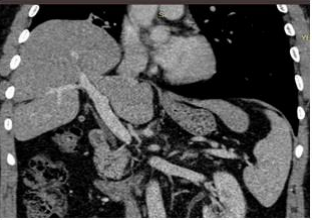

The subsequent thoracic CT demonstrated the rupture of the right hemi-diaphragm and hepatic herniation into the right hemithorax (Figure 2). Due to this life-threatening emergency situation of the hemodynamically unstable patient, thoracotomy was performed through the 6th intercostal space. Diaphragmatic dislocation was observed extending from the hemidiaphragmatic chest wall to the anterior lateral rib cage. The liver was completely surrounded by the chest wall, with the upper part of the chest wall facing upwards (Figure 3). After positioning the liver back into the abdominal cavity, the diaphragmatic rupture side was closed with silk 2-0 sutures, and the diaphragm was then repositioned in the rib cage. Any adverse event was not detected during the 14-month follow-up period.

Figure 2